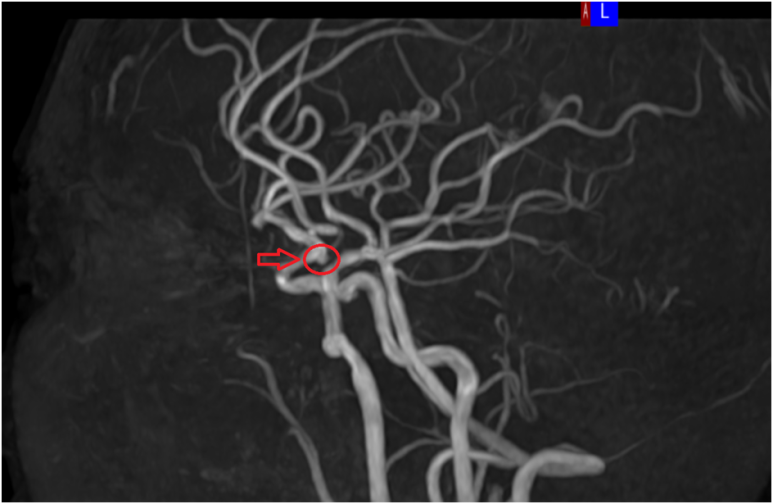

MRI는 뇌종양, 뇌염, 뇌혈관 질환, 미세출혈 등

CT로는 보기 어려운 병변까지 파악할 수 있어,

근본적인 두통의 원인을 찾는 데 매우 중요한 검사입니다.